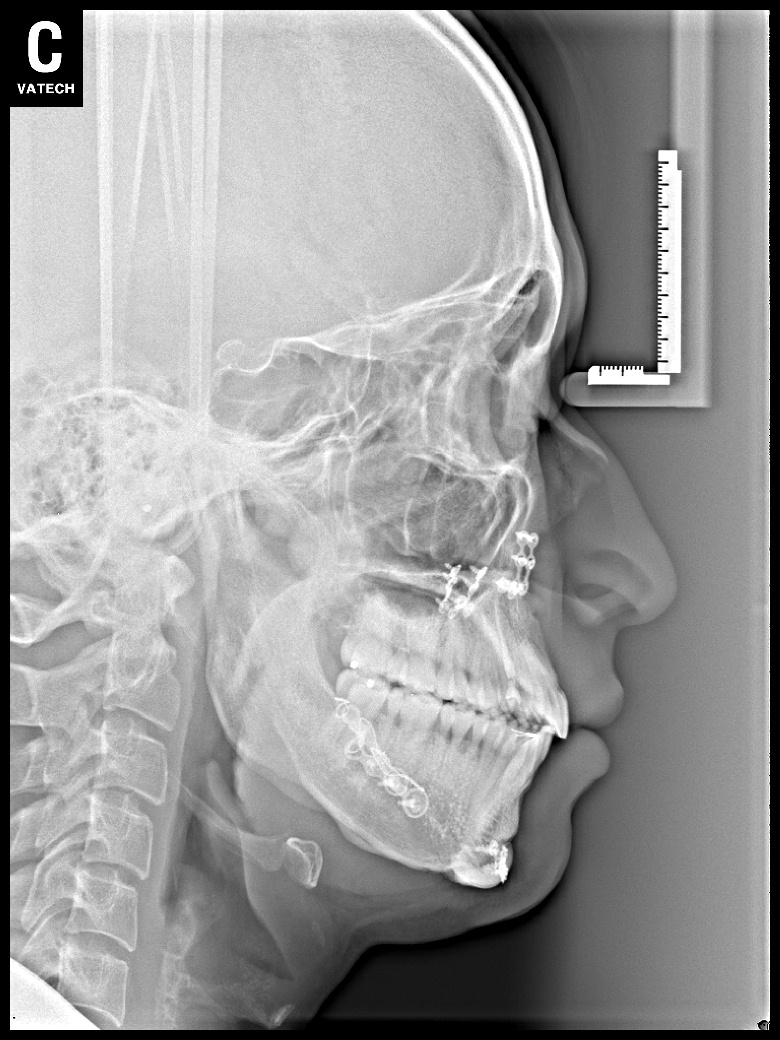

치료 전 사진입니다.